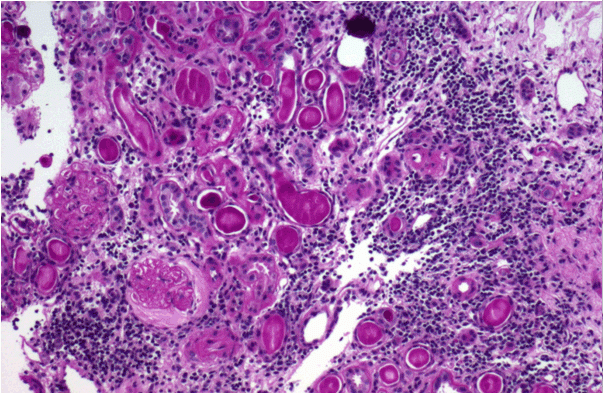

실제로 사구체신장염은 조기에 발견된다면 즉, 사구체경화증이 없거나 세뇨관 위축이 심하지 않은 경우는 적극적인 치료로 완치시킬 수 있다. (그림4/5)